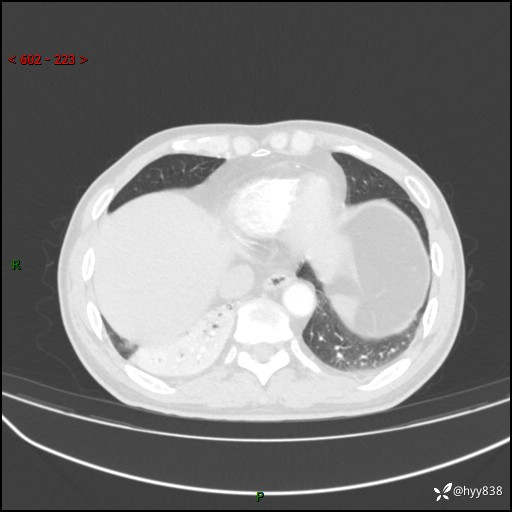

63岁/男,发热5余天。精彩好病例,“大叶性肺炎”,等你来诊---结果公布~

【患者信息】:63岁/男

【主诉】:发热5余天

【现病史及既往史】:患者5余天无明显诱因出现畏寒寒战发热,最高体温39.5℃,发热无明显昼夜规律,伴全身乏力、头晕,无头痛、无咳嗽咳痰、无胸痛咯血、无气短、无腹痛腹泻、无尿频尿急尿痛等不适,于当地市第五人民医院就诊,予以抗感染等治疗(具体不详)后发热无明显好转,1天前查胸部CT提示右下肺感染,为求进一步诊治,门诊以“社区获得性肺炎”收治入院; 起病以来,患者精神、食欲一般,睡眠可,大小便正常,体力体重较前无明显变化。

【检查】:胸部CT增强